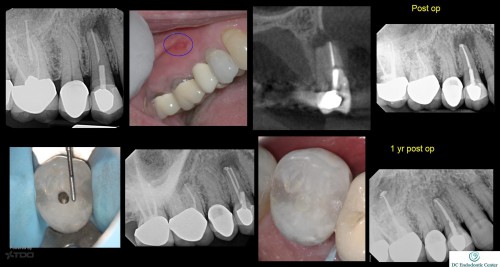

#30 – Soffit Access Preparation

#30 Soffit access prep with incomplete de-roofing of the pulp chamber offers good resistance form […]